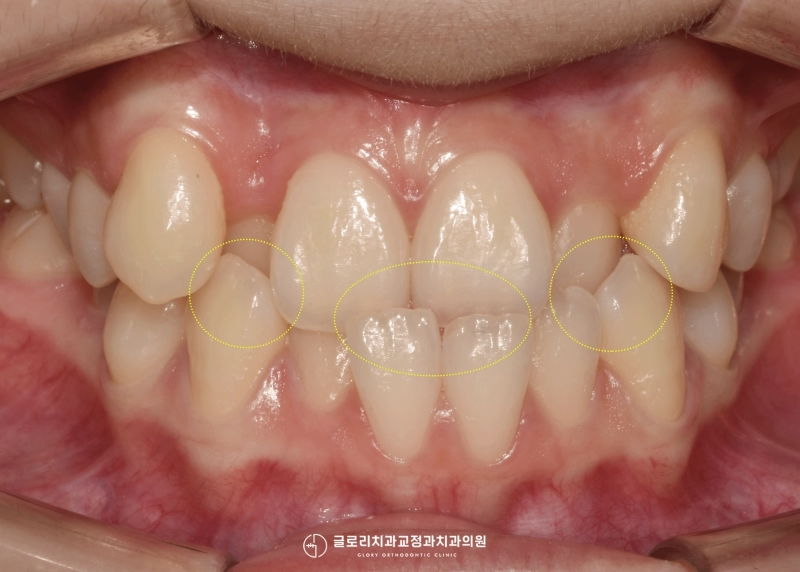

시간의 흐름에 따라 서서히

움직이는 과정들을 볼 수 있었습니다.

그중 눈에 띄는 움직임을 볼 수 있었던 곳은

송곳니 부분이었는데요.

이전에는 위로 솟은듯한 느낌으로

눈에 먼저 띄곤 했지만,

이제는 본래 송곳니 자리를 잘 찾아와

정렬이 잘 되어가고 있는 모습을 보여줍니다.

여기 발치로 인해 생긴 space도

폐쇄를 시키려면 앞으로 1년 정도

더 지켜보아야 됐는데요.

공간을 폐쇄시키기 위해서

파워 체인(power chain)을 체결해

회전과 이동을 도왔습니다.